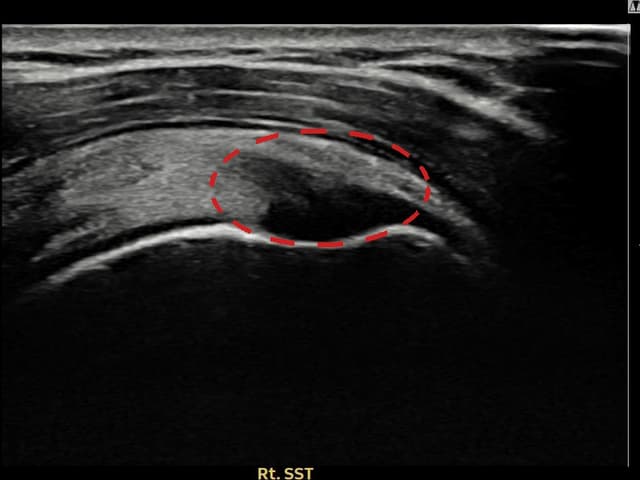

右侧 冈上肌腱 石灰化肌腱炎

10mm × 7mm